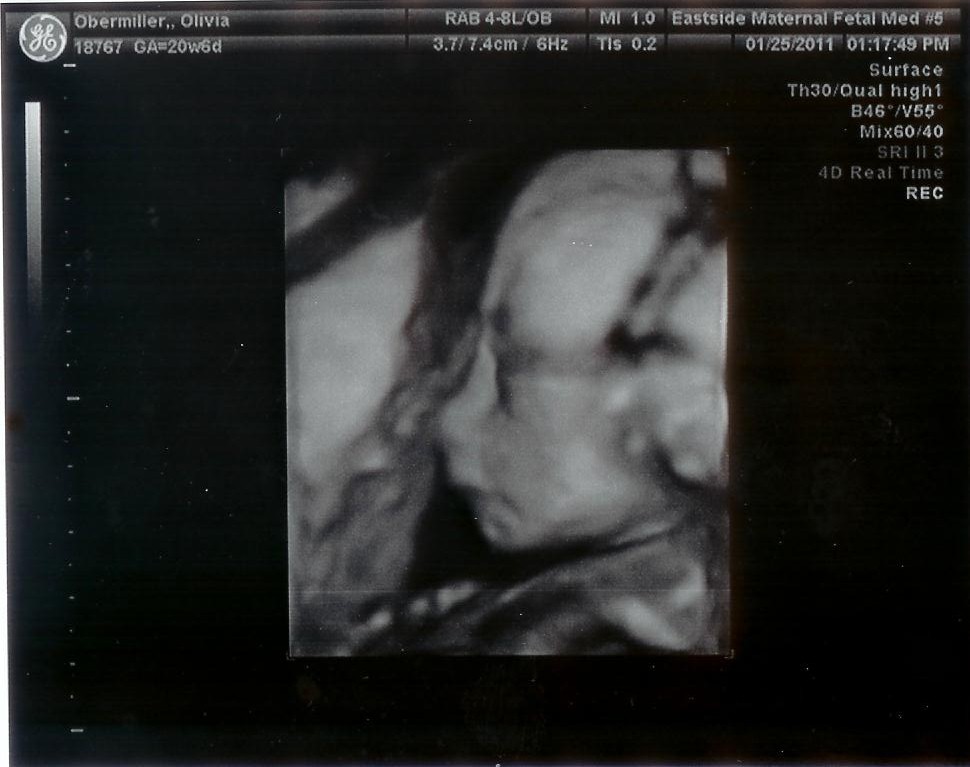

Early to bed and early to rise...the baby has been waking Olivia up quite early lately (baby kicked hard just now to say hello). Today we went to our 20 week ultrasound. We didn't know what to expect, and we were surprised when they said it would take about an hour. It turns out that there is a lot to inspect on that little body. The ultrasound operator spent about half an hour looking at the heart, head, arms, legs, and just about every other part of the baby. She had us look at each other when she checked the sex, since I guess at this point it is pretty obvious. So only two people (the operator and the doctor who checked it after) know the sex of the baby, not even Olivia's OB knows. They also took some interesting 3D pictures, although most didn't turn out because the umbilical cord was in the way.

Profile picture of baby!

The baby was upside-down the whole time, with the head pressing directly on Olivia's bladder, which explains all the frequent trips to the restroom! To see all the different sides of baby, Olivia had to tilt back in the patient's chair in hopes that baby would turn to orient himself. Eventually she got all the shots she needed, and we have a really long video to cut down for you to see as well. At the end we found that everything is okay and normal, except that Olivia is a bit underweight and needs to eat more. That will probably be the last time we get to see baby before June, so now we just get to feel the kicks and punches for a while. Also, Olivia has been sore from all the growing, and since she wasn't supposed to go to the chiropractor, we finally went to see the physical therapist recommended by her doctor. He gave her a few stretches to do in the morning and before bed, so hopefully she won't be so sore.